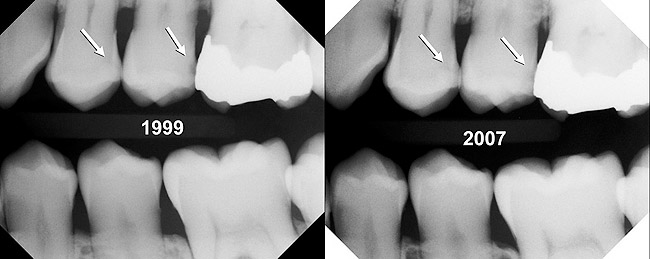

Some may argue that this treatment is supervised neglect or undertreatment. In the past, without good risk assessment and effective management of the biofilm disease, that may have been the case. With the current (and improving) understanding about the management of a biofilm imbalance and the use of risk assessment, this is no longer the case. As an example, a patient presented in 1999 with 2 interproximal radiographic lesions on teeth Nos. 12 and 13 (Figure 7). The radiographs are only a snapshot in time. By understanding the patient’s risk profile, immediate treatment was not indicated. This decision has been validated by examination of her radiographs from 2007, which show these lesions were from a historic cariogenic episode and were no longer progressing.

Figure 7  Nonprogression lesions in a patient who is currently at low risk, although it is obvious that there had been a period of high risk.